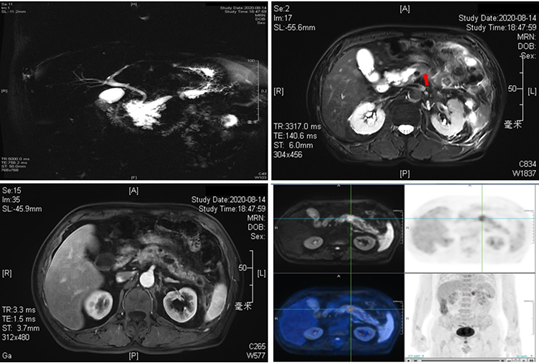

患者男性,63,因“腹胀3月余”就诊。患者3月前无明显诱因下出现左上腹腹胀,伴左腰背部不适感,进餐后、左侧卧位加重,无明显腹痛,无恶性呕吐等不适,当时未予重视。患者3周前至外院就诊,查腹部增强CT示胰头多发囊性灶、主胰管不均匀扩张、考虑IPMN,胰腺炎改变伴周围渗出,胆囊炎。后于2周前至我院就诊,行超声胃镜检查示胰头钩突见一大小约24×27mm囊实性占位,累及部分胰体,病灶紧邻门静脉,考虑IPMN恶变可能。8月14日我院腹部增强MRI示胰腺IPMN(混合胰管型),胰颈部病灶局部恶变可能,胰尾渗出、假性囊肿形成。8月17日我院PET/CT提示:1.考虑为胰腺体部MT伴远端胰腺体尾部、周围腹膜炎症及胰尾假性囊肿形成可能;2.胰腺头部及钩突良性病变可能,胰管扩张,胆囊炎。患者两周前血常规示WBC 16.69×10^9/L,N 80.9%,目前予以头孢呋辛抗感染治疗中。患者精神可,食纳可,夜眠可,二便无殊,体重近期下降2.5Kg。我院MDT团队专家就该患者诊断及后续治疗方案展开讨论。

影像科王明亮教授阅患者影像资料后认为:MRI提示胰头多房囊性灶,与主胰管相通,胰管明显扩张,符合IPMN影像学表现。DWI序列可见胰体病灶,远端胰管扩张,胰尾部可见渗出及囊性灶。结合PET结果,考虑胰头为IPMN, 扩张胰管里没有乳头状的增生,远端胰管的扩张和增强模式符合导管腺癌。故考虑胰体为导管腺癌,引起远端胰管扩张合并假性囊肿。

核医学科顾颖涛教授阅患者PET报告后认为:PET/CT图像示胰腺体部见糖代谢异常增高(最大SUV值约为6.1)的稍低密度灶,大小约15.6×14.5mm,其在PET/MRI图像上呈T1WI低信号、T2WI及DWI呈高信号,最大SUV值约为5.0;病灶远端胰腺体尾部弥漫性糖代谢稍增高,周围腹膜片絮状增厚、部分伴糖代谢异常增高,胰尾旁增厚腹膜区域见囊状低密度灶,考虑胰体MT伴远端体尾部炎症及胰尾假性囊肿形成。胰腺头部及钩突见多房囊状低密度灶,与主胰管分界不清,大小约为40.5×32.2mm,最大SUV值约为1.4,其在PET/MRI图像上呈T1WI低信号、T2WI及DWI高信号,最大SUV值约为1.1,胰头病灶考虑IPMN可能大。